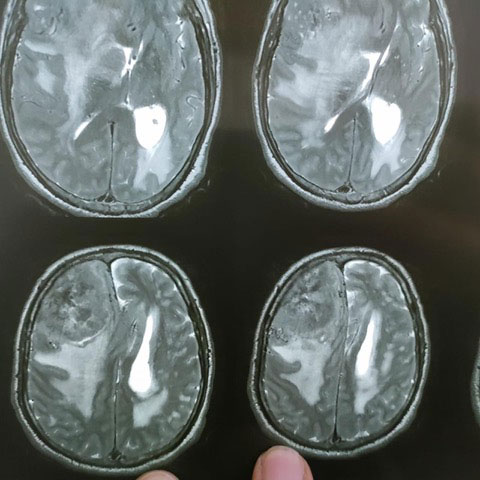

Dr. Ujwal Yeole is an experienced neurosurgeon specializes in treating a wide spectrum of neurological conditions including neuro-oncology, peripheral nerve disorders, vascular disorders, spinal pathologies, pediatric neurosurgery, neuro-trauma and skull base neuroendoscopic procedures.